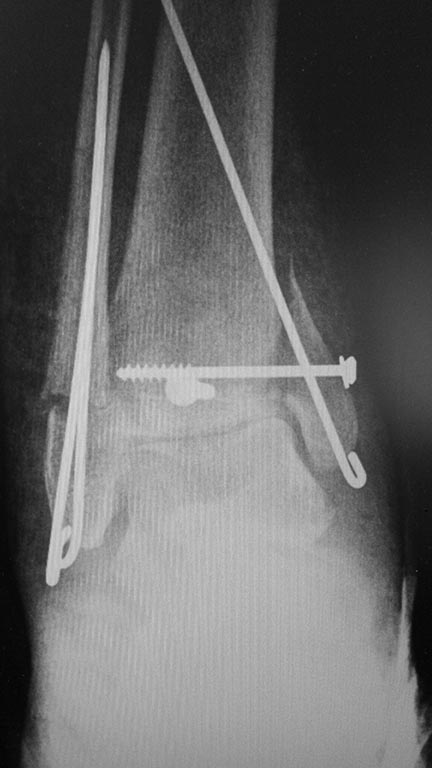

Мужчина, 1987 г.р. получил травму 10.2014. ДТП. Закрытый двухлодыжечный перелом костей костей левой голени, перелом заднего края большеберцовой кости с подвывихом стопы кзади, кнаружи.

Наложен дистрактор. Операция 10.2014: закрытая репозиция, остеосинтез спицами, винтами. В дальнейшем произошло ожидаемое усугубление нарушений взаимоотношений в голеностопном суставе.

Какой план лечения,на Ваш взгляд, предпочтительнее в данном случае? Возможно ли одномоментно устранить подвывих или только на аппарате Иллизарова? Первичные снимки после травмы отсутствуют. Критично ли "растоптана" латеральная суставная поверхность большеберцовой кости?